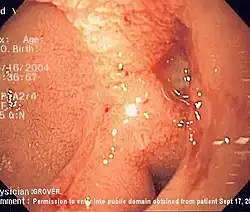

Upper gastrointestinal bleeding is from a source between the pharynx and the ligament of Treitz. An upper source is characterised by hematemesis (vomiting up blood) and melena (tarry stool containing altered blood). About half of cases are due to peptic ulcer disease (gastric or duodenal ulcers).[3] Esophageal inflammation and erosive disease are the next most common causes.[3] In those with liver cirrhosis, 50–60% of bleeding is due to esophageal varices.[3] Approximately half of those with peptic ulcers have an H. pylori infection.[3] Other causes include Mallory-Weiss tears, cancer, and angiodysplasia.[2]

The benefits versus risks of placing a nasogastric tube in those with upper GI bleeding are not determined.[4] Endoscopic evaluation within 24 hours is recommended,[4] in addition to medical management.[35] A number of endoscopic treatments may be used, including: epinephrine injection, band ligation, sclerotherapy, and fibrin glue depending on what is found.[2] Prokinetic agents such as erythromycin before endoscopy can decrease the amount of blood in the stomach and thus improve the operators view.[4] They also decrease the amount of blood transfusions required.[36] Early endoscopy decreases hospital and the amount of blood transfusions needed.[4] A second endoscopy within a day is routinely recommended by some[16] but by others only in specific situations.[22] Proton pump inhibitors, if they have not been started earlier, are recommended in those in whom high risk signs for bleeding are found.[4] High and low dose PPIs appear equivalent at this point.[37] It is also recommended that people with high risk signs are kept in hospital for at least 72 hours.[4] Those at low risk of re-bleeding may begin eating typically 24 hours following endoscopy.[4] If other measures fail or are not available, esophageal balloon tamponade may be attempted.[2] While there is a success rate up to 90%, there are some potentially significant complications including aspiration and esophageal perforation.[2]